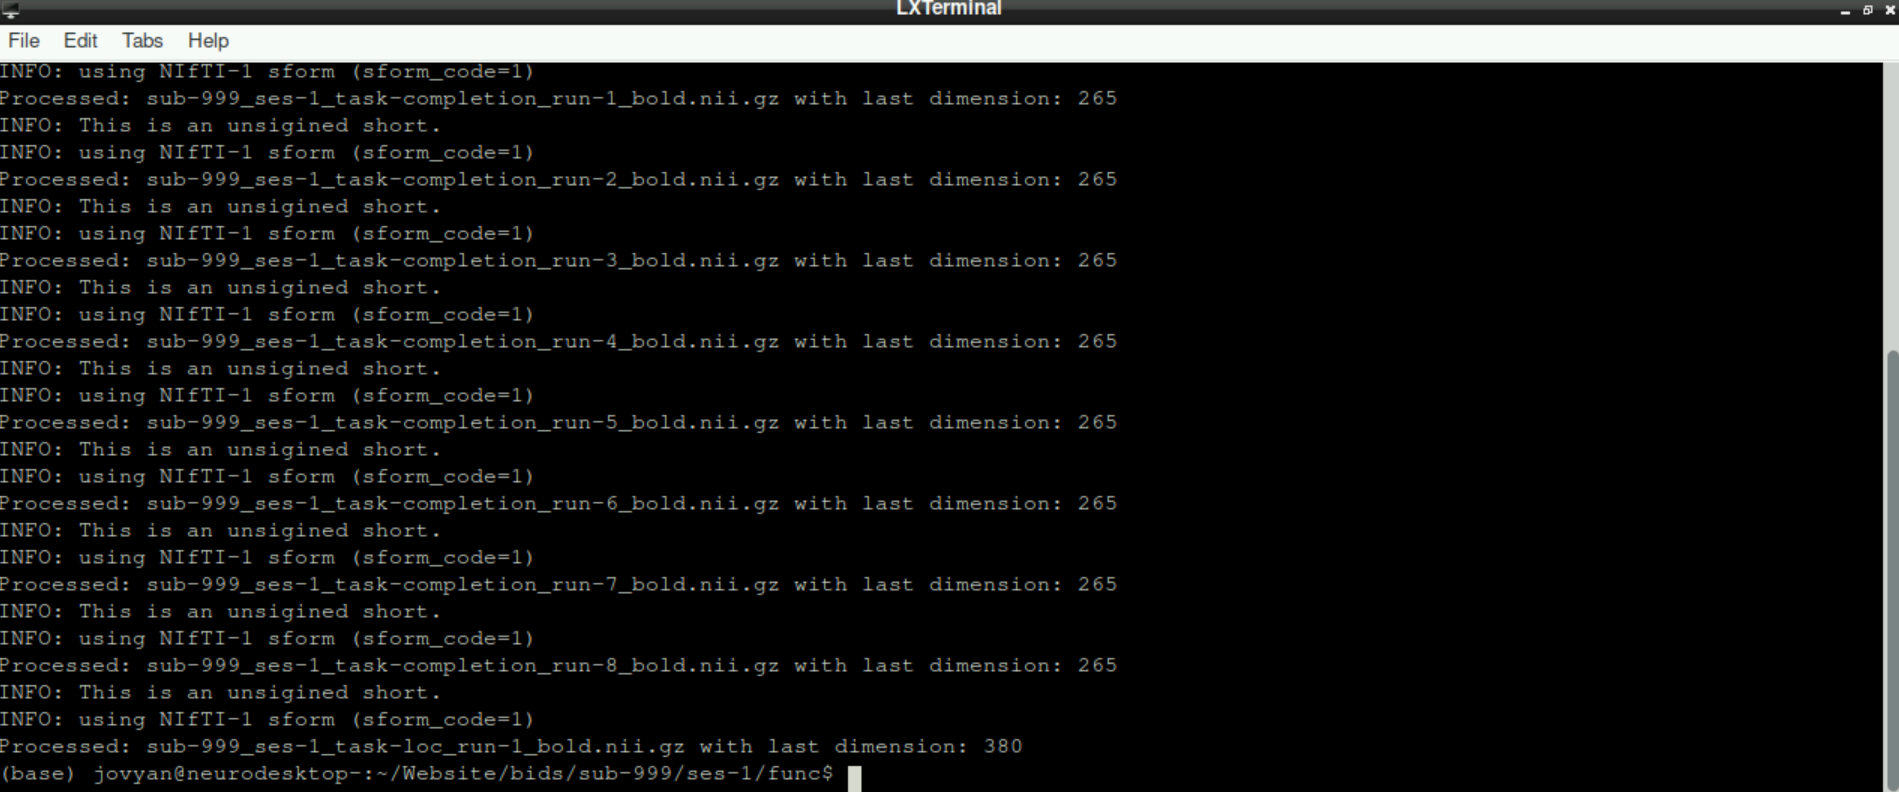

This process can take a while, especially in the beginning. Don´t get stressed out, when nothing happens for a while and only info statements get printed, be patient!

After some time, you will get the information, that the first nifti is processed. This will be repeated for all files in your working directory that end in _bold.nii.gz. Since the working directory is set to our func directory, the functional scans of all runs and potential functional localizer runs will be processed automatically: